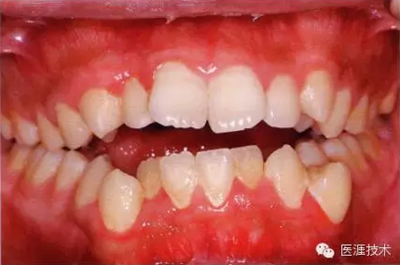

22歲男性牙齦炎的臨床圖像

22歲男性,抽煙(1天約15根,煙齡5年)。刷牙狀態(tài)不佳。抽煙者特有的纖維性牙齦,未見發(fā)紅、腫脹。探針觸診,所有部位均出血。X線牙片未見骨吸收,診斷為牙齦炎。